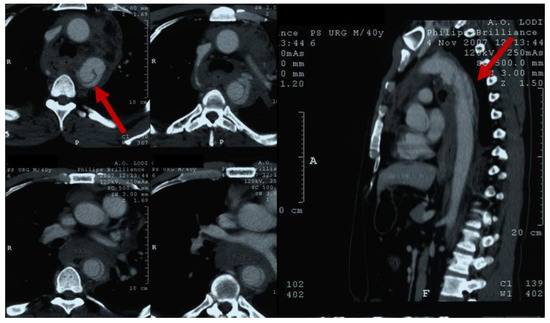

2. Clinical Features of BTAI

3. Diagnosis

4. Aortic Injury Grading